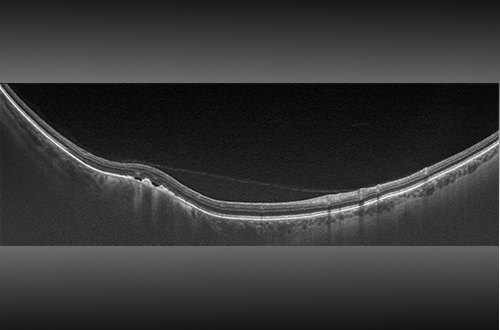

Swept-Source OCT

Swept-source facilitates examination of the retina from vitreous through the choroidal-scleral interface. The SS-OCT and UWF combination produces a 200° single-capture optomap image in less than ½ second and enables guided OCT scanning across the retina and into the far periphery. The image shown is a 23 mm line scan.